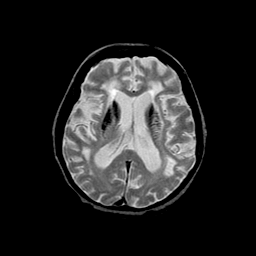

Basal Ganglia Calcification: T2-weighted MR -- Slice #10

[Home][Help][Clinical] Slice 10